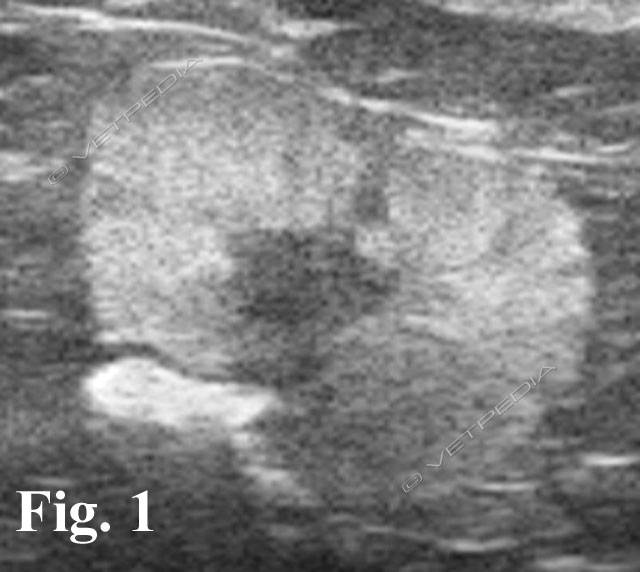

Le modificazioni comportamentali secondarie a patologie organiche sono relativamente frequenti e giustificano la realizzazione di un’accurata visita clinica nell’ambito della consultazione comportamentale (Fig. 1). La diagnosi comportamentale, grazie al modello proposto da P. Pageat, può inserirsi in un contesto di diagnosi differenzia...